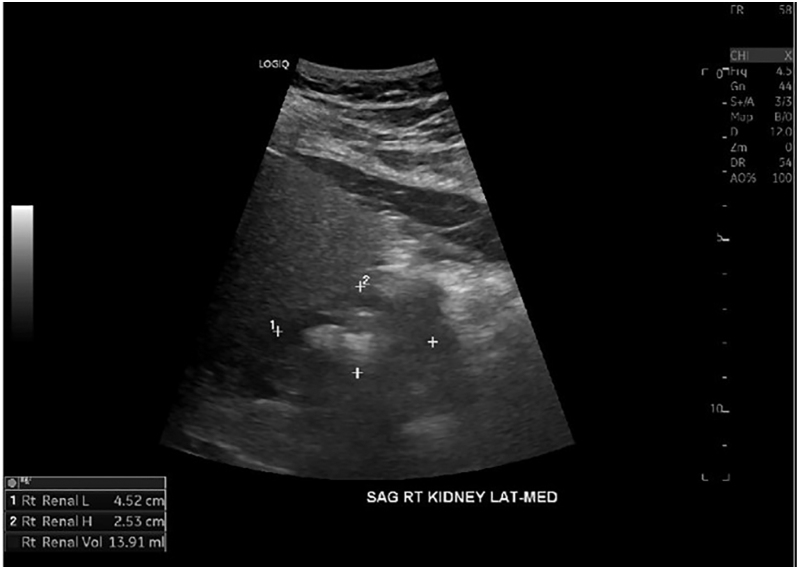

Summary: HDR is a rare autosomal dominant genetic disorder characterized by the triad of hypoparathyroidism, sensorineural deafness and renal anomalies caused by haploinsufficiency loss of function of the GATA-binding protein 3 (GATA3) gene. We present a case of a 56-year-old male diagnosed with hypoparathyroidism, sensorineural deafness, renal hypoplasia and epilepsy. Genetic testing revealed a novel GATA3 heterozygous mutation c.860C>A with a predicted amino acid substitution p.Ala287Asp. This hitherto unreported missense GATA mutation was characterized by a relatively late-onset and milder phenotype of the HDR triad.

Learning points: GATA3 gene mutations located on chromosome 10p cause haploinsufficiency of the GATA3 protein affecting fetal development of the parathyroid glands, inner ear and renal anomalies, resulting in HDR syndrome with an autosomal dominant inheritance pattern.Also known as Barakat syndrome, it has been reported in less than 200 cases with an identified mutation, each having a varied phenotypic presentation without consistent genotypic correlation.We present a patient with HDR syndrome who tested positive for a novel mutation c.860C>A, resulting in a missense substitution of amino acids p.Ala287Asp in the GATA3 gene.Clinicians who identify this rare triad of hypoparathyroidism, sensorineural deafness and renal anomalies should further investigate with genetic testing for GATA3 mutations.